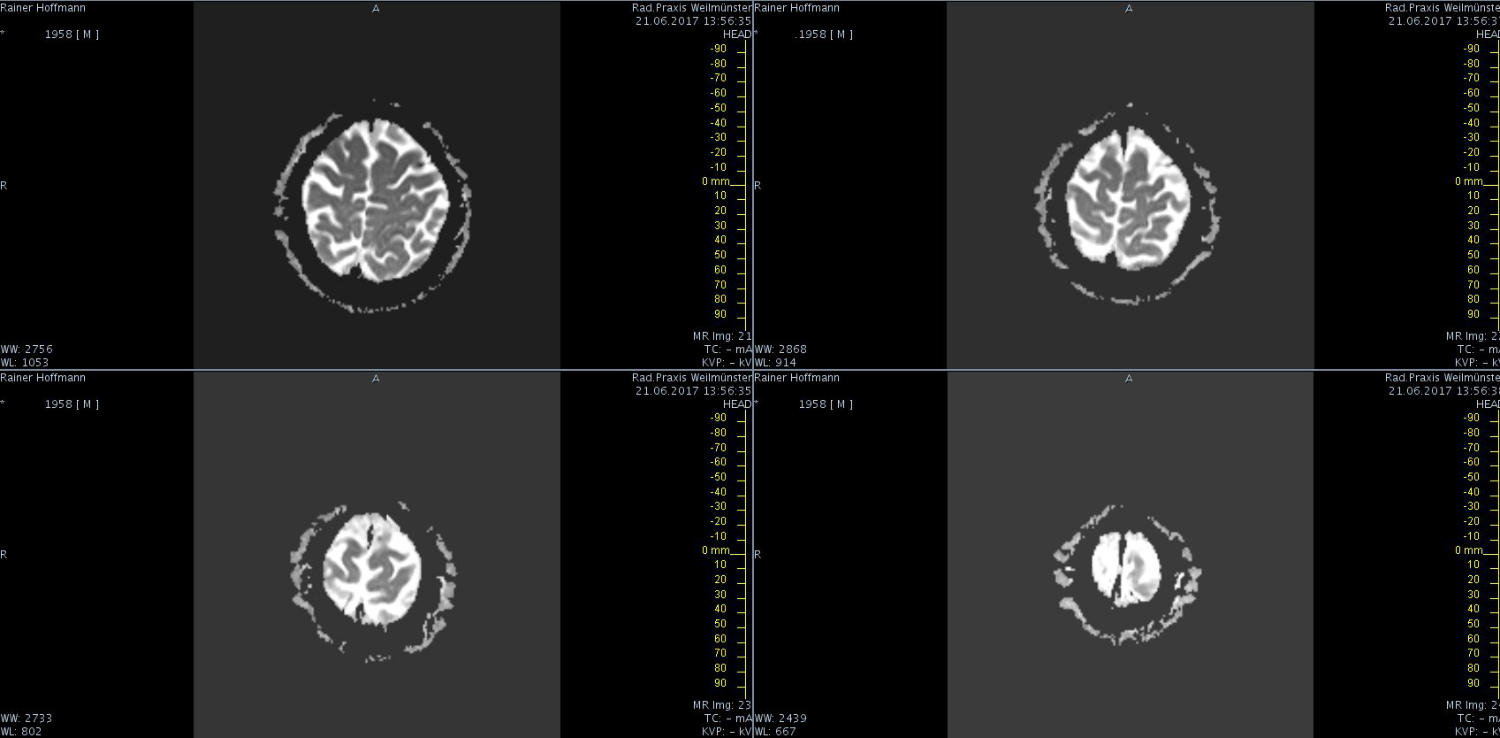

Das ist ja ganz toll, dass Ihr die Seite so schnell gefunden habt. Ich zeige euch jetzt ein ganz, ganz anderes Paßfoto von mir. Es könnte Ähnlichkeiten zu anderen lebenden oder bereits verstorbenen Personen geben. Wenn Ihr das erste Bild oben links anklickt wird es ver- größert dargestellt. Dann kann man mit den Pfeiltasten am unteren Bild- rand durch meinen Kopf blättern. Es gibt nicht viel zu sehen. Vielen Dank an Martina für Ihre Hilfe.

MRT